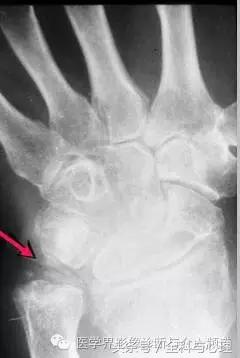

4、痛风石

为尿酸盐沉积形成,发生在关节周围软组织、包括韧带、肌腱、滑囊,眼、耳、鼻、喉、皮肤, 50%的钙化为X线平片可见。

痛风石,可见软组织肿胀及钙化灶。